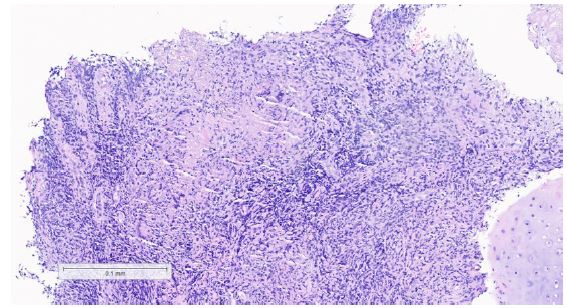

The patient was admitted to the hospital with a diagnosis of pulmonary tuberculosis with laryngeal involvement. A CT thorax performed, showed findings consistent with radiologically established pulmonary tuberculosis with upper zonal predominance (Figure 2). A CT neck on the same day revealed mild thickening of the epiglottis, particularly on its cranial aspect, and mild superficial enhancement at the level of the supraglottis (Figure 3).

Figure 2: CT Thorax showing tree-in-bud segments in the apical segments of bilateral lower lobes, along with a cavitating lesion in the right lung.